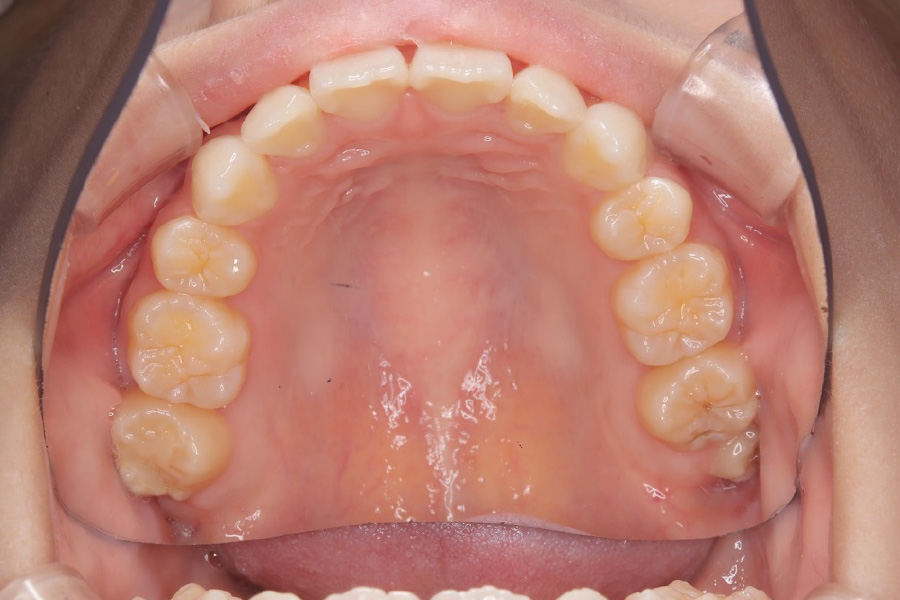

治療後

主訴 歯のスペースを閉じたい

期間 2年

治療内容 インビザライン矯正

非抜歯

治療に伴うリスク 矯正終了後は、リテーナーを指示通りに使用し、歯の後戻りを防ぐ必要があります。